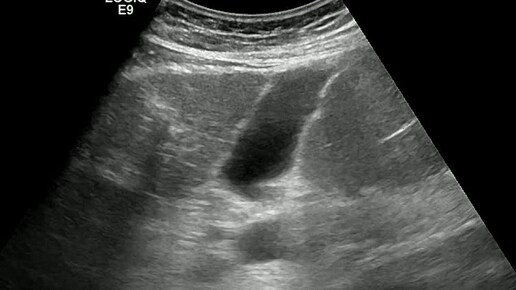

Видео к статье "Внутрипечёночный желчный пузырь" https://dzen.ru/a/Z9O7lrJKKgcKCx1N

Ультразвуковые находки от врача УЗД Зорина Я.П.